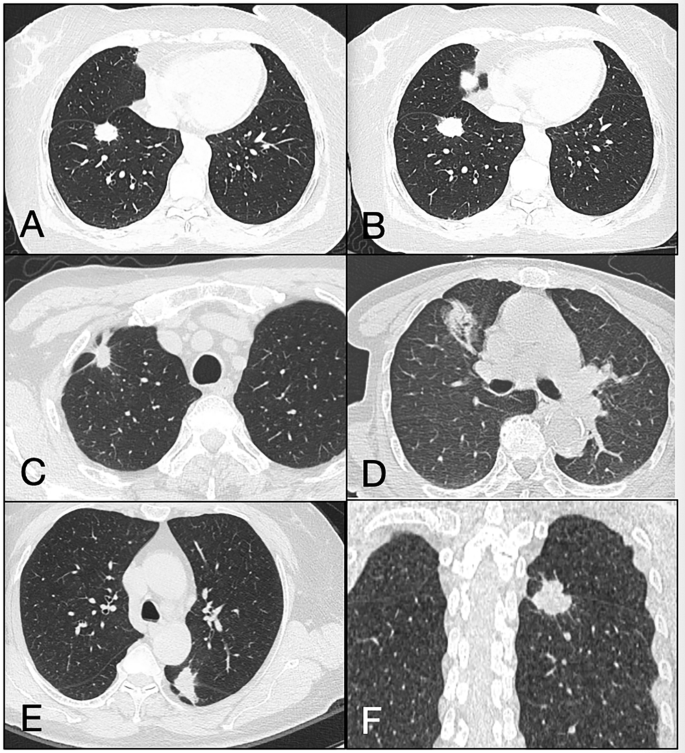

Among the PSNs and SNs, there were 160 pleural-attached nodules (24, 15% VPI positive), 194 pleural-tag nodules (23, 11.86% VPI positive), and 5 nodules pushed against the pleura (all VPI positive) (Fig. 4).

Representative images of the pleural-attached nodule (A, B), pleural-tag nodule (C, D) and nodule pushed against pleura (E, F). Different slice of the same nodule in CT image of a right lower lobe pleural-attached nodule with pleural indentation (A, B). The nodule surface directly touched the pleura surface. Axial CT (C, D) showed a right upper lobe pleural-tag nodule. There was one or more linear tag between the nodule and pleura, but the nodule does not directly touch the pleura. Axial CT (E) and coronal CT (F) showed a left lower lobe nodule pushed against the interlobar pleura.

Univariable analysis revealed the statistically significant features according to the VPI status. Multivariable logistic regression identified nodule type (OR, 4.86; P = 0.036], solid component mean diameter (cut-off value: 15 mm; OR, 4.67; P = 0.024) of pleural-attached nodules, and solid component mean diameter (cut-off value: 13 mm; OR, 3.94; P = 0.026), and PIF (cut-off value: 0.405; OR, 23.32; P = 0.003) of pleural-tag nodules as independent predictors for VPI, with the exception of the jellyfish and bridge tag signs (Supplementary Table 3).